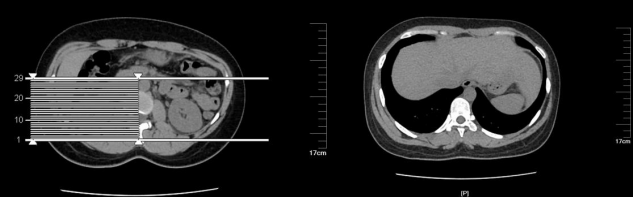

图12 详细的病理组织图(2)肾上腺CT检查,如图13-14。

图13 肾上腺CT报告

图14 肾上腺CT图案例分析嗜铬细胞瘤是一种少见的内分泌疾病,临床表现多样,且疾病演变较快有些患者可以完全没有症状,有症状的话最典型的是高血压,发作时最常见的三联征头痛、心悸、多汗症状就如这案例中的患者是在日常健康体检中发现的嗜铬细胞瘤,且血压都升高4年多,知道后却不管不问,也很容易出现问题。